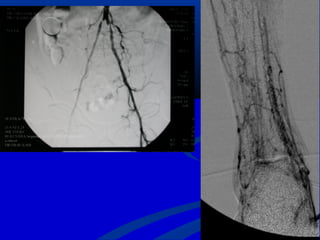

 AngiographyAngiography often foot vesselsoften foot vessels

preservedpreserved

 RevascularizationRevascularization

 AngioplastyAngioplasty

 Distal venous bypassDistal venous bypass